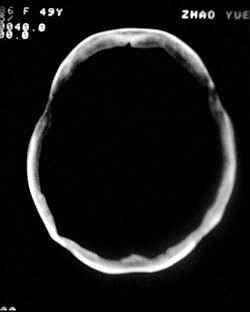

1.颅骨对称性、形态规整性增厚,应属发育异常。四叠体池左后侧单发点状钙化,无其他阳性表现,多属正常,不需要过多关注。

2.双侧基底节区域多发性梗塞灶。

1.双侧基底节区腔梗。

2.颅骨内外板广泛性增厚,板障狭窄甚至消失,双侧对称。无明显相应临床症状。考虑“泛发性骨皮质增厚症”。可进一步检查下颌骨及管状骨骨干。(下颌骨骨小梁增多、密集,密度增高亦为本病特点,管状骨骨干皮质向内增厚引起骨皮质厚度增加,骨密度增浓、髓腔狭窄但不消失,骨干周径较少增加)。与石骨症鉴别,后者很少影响颅盖骨和下颌骨,管状骨改变主要累及干骺端和骨骺,而骨干皮质较少增厚,椎体和髂骨翼有特征性表现。

“泛发性骨皮质增厚症,又称骨内膜增生症(endosteal hyperostosis):分为常染色体隐性遗传性疾病(van buchem)和常染色体显性遗传性骨硬化症(worth病)。后者更少见,亦较轻。两者的病理上均为骨内膜 成熟的板状新生骨形成,髓腔变窄。颅骨、颅底骨 、下颌骨,肋骨、四肢骨及骨盆骨、脊柱均可见骨内膜增生,髓腔变窄或消失,但骨外径不加大,骨骺不累及。”

本例的确应该这个病。建议楼主检查病人其他部位有无类似表现,以便确诊。